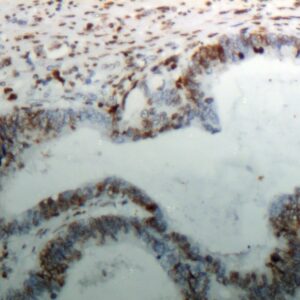

BioGenex has pioneered the development of miRNA research and diagnostics tools with leading-edge products. Currently, we offer over 240 ready-to-use (RTU) Super Sensitive™ Nucleic Acid (SSNA) miRNA ISH probes for accurate and early tumor diagnosis. These probes are sensitive enough to detect low-abundant miRNA(s) that are often required to identify biomarkers. They have a high melting temperature enabling stringent washes to remove non-specific binding. BioGenex miRNA probes are dual-end labeled with an anti-fluorophore to amplify the signal and yield clean and intense staining.